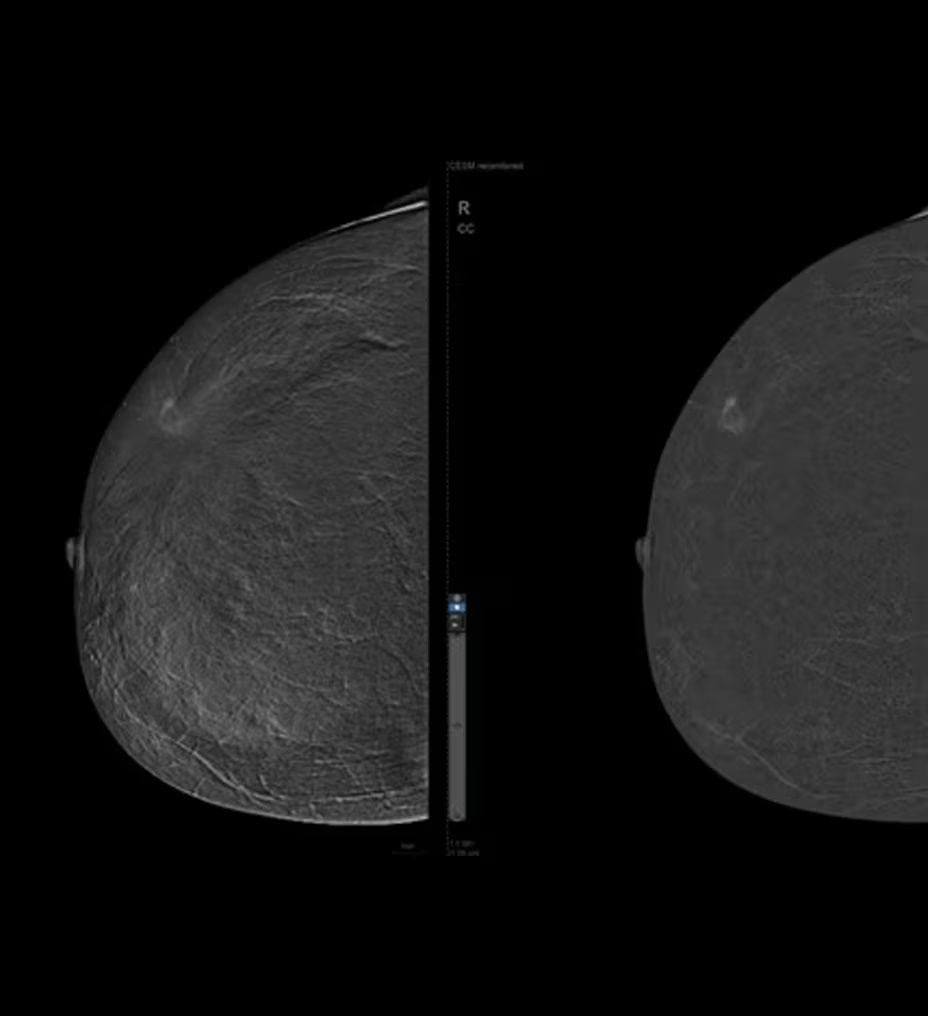

SenoBright™ HD

Contrast-Enhanced Mammography advanced application

Reduces the masking effect of breast tissue to reveal what matters1

Astonishing clarity

The image you need is never out of reach

• Helps reduce the masking effect of fibroglandular breast tissue and increases the tumour signal1.

• Contrast agent highlights areas of unusual blood flow.

• CEM is an alternative imaging method to MRI, especially when MRI availability is limited, and for patients for whom MRI is contraindicated5.

Exceptional performance

Improve clinical accuracy

• Find lesions that cannot be seen on routine mammography6,7,8.

• Provide high specificity for low false-positives1.